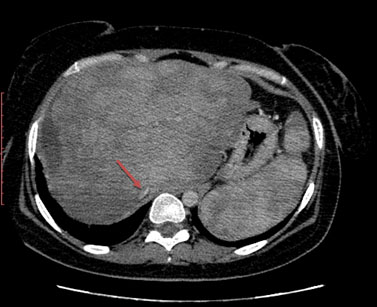

Abdominal CT showed multiple hepatic and splenic nodules enhanced after contrast injection, multiple peritoneal and retroperitoneal lymphadenopathies, and a lack of individualization of hepatic veins. The portal vein and its branches were permeable (Figure 1, Figure 2, Figure 3).

Figure 1: Abdominal CT with injection of contrast medium at venous time showing multinodular liver and spleen, with no visualization of the hepatic veins and a laminated inferior vena cava (red arrow).

Figure 3: Abdominal enhanced CT at venous time showing heterogeneous nodular hepatomegaly with mass effect on the inferior vena cava which is laminated (red arrow).